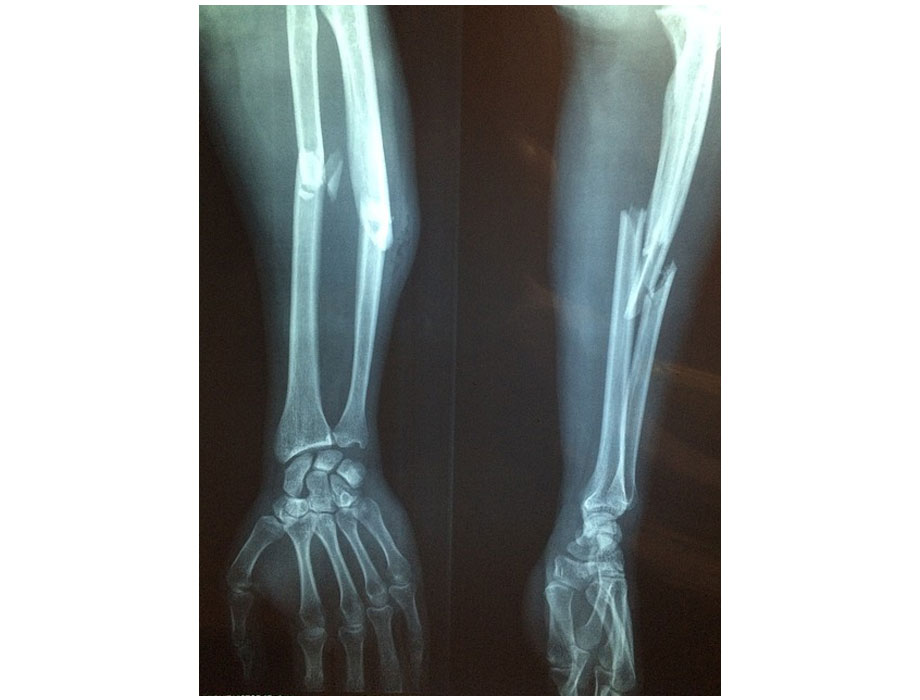

- Mito. La osteoporosis sólo provoca dolor en el cuerpo. El dolor ocasionado por esta condición no es menor y puede llegar a extenderse principalmente hacia la espalda, cadera y muñecas. Sin embargo, una de las complicaciones más graves y que preocupan a los especialistas son las fracturas óseas.

Según la Fundación Internacional de Osteoporosis (IOF), a nivel mundial se produce una fractura osteoporótica cada tres segundos. En México, el 75% de las fracturas osteoporóticas afectan a mujeres; una de cada 12 personas mayores de 50 años sufrirá una fractura de cadera, con consecuencias graves como incapacidad para caminar de forma independiente. Estas fracturas pueden desencadenarse por una caída, sin embargo, en casos extremos, los huesos pueden debilitarse tanto que lleguen a fracturarse por sí solos.